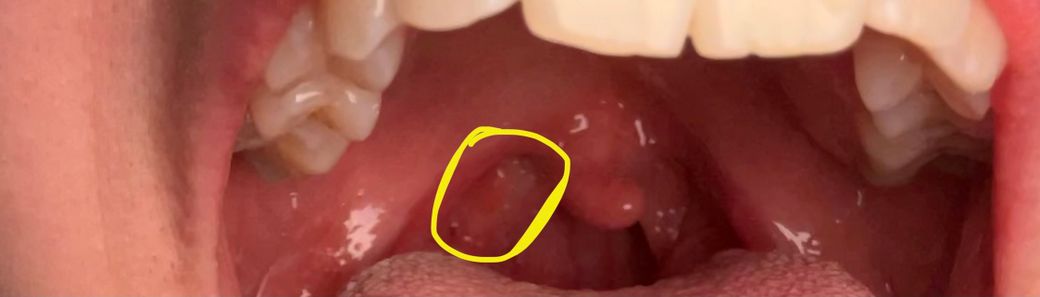

요즘 목에 이물감이 생겨서 인터넷에 찾아보니까

편도결석이 원인일수 있다고 하는데

동그라미 친 부분이 편도결석 일까요?

아니라면 비염이 원인일수 있는지 궁금합니다.

편도결석에 대해 걱정스러우시군요. 사진으로 잘 보이지는 않지만 편도결석을 의심할만한 부분은 보이지 않습니다. 목에 염증만 있어도 이물감이 느껴질 수 있으니 진통제를 복용해보시고, 그래도 나아지지 않는다면 이비인후과를 방문해보시길 권해드립니다.